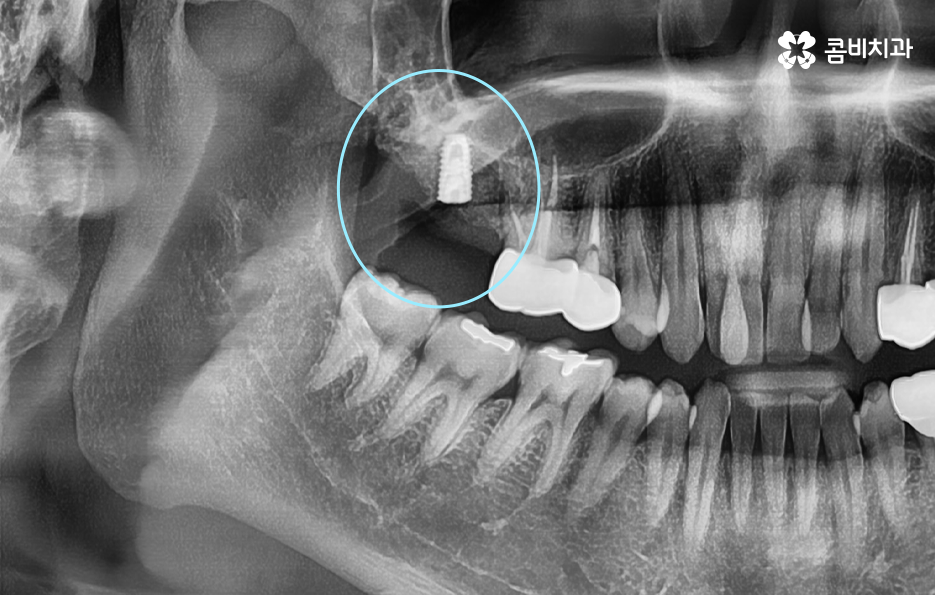

이미 신경치료를 했던 치아라고 해도 보철물 제거 후에 충치를 잘 치료하고 재신경치료를 통해서 치아를 보존할 수 있는 경우가 있고 발치 후 임플란트를 해야하는 경우도 있는데요

이러한 판단 기준은 치아 내부에서 충치가 발생되었을 때 충치가 얼마나 치아 뿌리 쪽으로 깊어졌는지 혹은 살릴 수 있는 치아가 얼마나 잔존하는지에 따라서 다르며 치과의사 역시도 치아 속을 확인해보고 충치를 제거해봐야 알기 때문에 치과의사의 숙련도, 경험도 중요하겠지만 치과의 내원 시점이 무척이나 중요하기 때문에 보철물이 오래된 경우에는 꼭 주기적으로 치과 검진을 하시고 의사의 소견 하에 크라운의 교체가 필요하다면 문제가 커지기 전에 재치료를 적절히 받는 것이 자연치아 보존에 중요할 거예요

어금니 충치 발치 후에는 바로 임플란트를 해야 하나요

위 사진에서 보여지는 것처럼 어금니는 치아 안쪽에 위치하고 있기 때문에 치아 상실 후에 심미적인 부분에 있어서는 당장 불편함을 못느낄 수 있지만 치아는 저마다 역할과 기능이 있고 저작력에 있어서 밸런스도 무척이나 중요하기 때문에 치아를 잃게 되었다면 별다른 이유가 없다면 즉시 임플란트 치료 계획을 세우시길 권하고 있어요

당장은 반대쪽 어금니로 식사를 해도 괜찮다고 느끼시는 분들도 있지만 장기적으로는 치아 저작력의 밸런스를 잃게 될 수 있고 그로 인해 소화불량이나 턱 관절 장애로도 이어질 수 있는데요. 임플란트를 즉시 권하는 더 중요한 이유로는 치아 발치 후에는 해당 잇몸 뼈가 서서히 흡수되기 때문에 주변 치열이 망가지거나 반대쪽 치아가 내려올 수 있으며 추후에는 임플란트를 하더라도 잇몸 뼈의 부족으로 인해 뼈이식을 추가적으로 해야 할 수 있다는 점에서도 임플란트 치료를 미루지 마시길 권하고 있어요